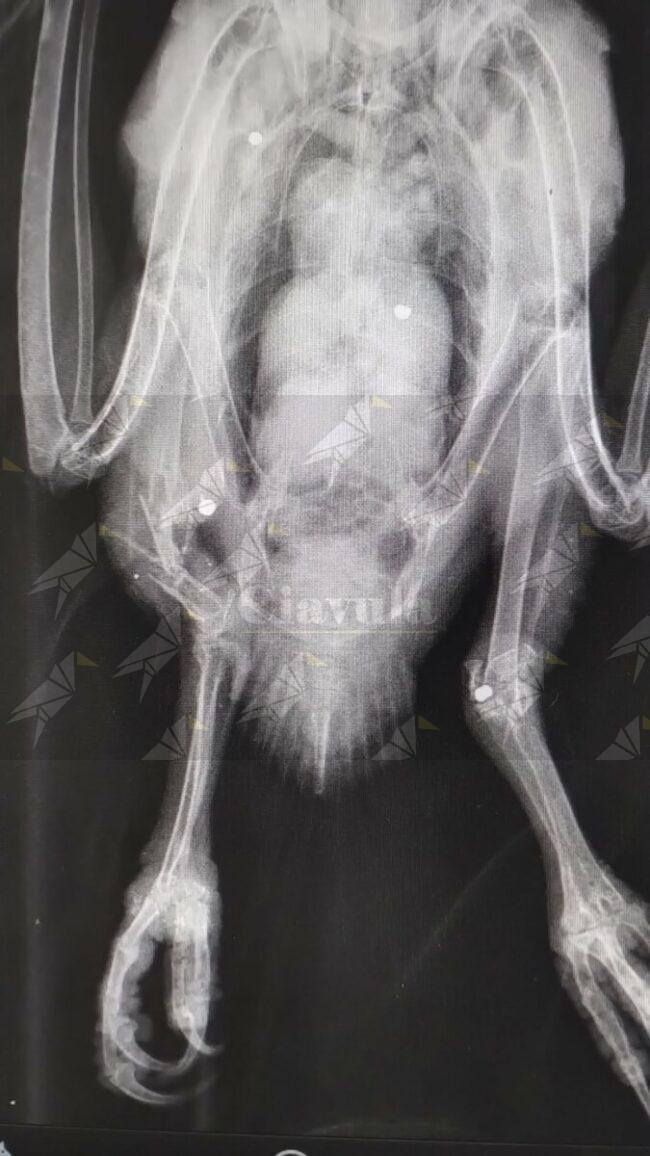

Qui, oltre alle indispensabili cure, è stato sottoposto a indagine

radiografica che ha evidenziato la presenza nel corpo di diversi pallini da caccia, uno

dei quali aveva purtroppo fratturato l’articolazione di una zampa. Si spera possa